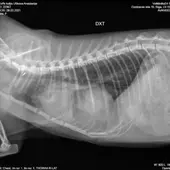

Хочу поделится своей историей покупки взрослой кошечки породы Девон рекс у заводчицы Zainaba Balabaja из питомника «Bambielf Mystery», которая в итоге оказалась больная, с врожденной деформацией диофрагмы, сросшимися органами, сжатым правым легким и еще кучей других проблем. Питомник зарегистрирован на имя её дочери Ирины Скобовы в Саласпилсе, по факту заводчица проживает и разводит котят в плявниеках. Если вкратце, весной 16го марта я приобрела у заводчицы кошечку породы Девон Рекс 4х лет, которая использовалась для разведения котят. Я и мой молодой человек созвонились с заводчицей и приехали к ней в скором времени посмотреть кошечку. В квартиру она нас не пустила, аргументируя тем что она и её муж возрастные, переболели ковидом и никого не пускают, а я наивная во все это поверила, так как это был мой первый опыт с заводчиками. Кошечку вывели на лестничную клетку в переноске, визуально она выглядела здоровой. Мы договорились об оплате наличными в размере 450 евро, о перерегистрации паспорта на меня и стерилизации через месяц в рекомендованной ей клинике, так как кошке недавно делали прививку. Договор и родословную она мне не выдала. Когда я забирала паспорт, она сказала что родословная нужна в том случае если я собираюсь водить кошку на выставки, и я решила не платить за перерегистрацию родословной на меня, так как не планировала кошку ни разводить, ни участвовать в выставках. Когда кошка начала жить у меня, спустя некоторое время у нее начали слезится глаза, заводчица уверяла что это из-за прививки. После я начала замечать что кошка часто чешется в районе подбородка и ушей, глаза все время слезились и она начала кашлять. После стерилизации кашель ухудшился, на что в клинике мне ответили что скорее всего кошка аллергик, сделали ей стероидный укол после чего симптомы прекратились на несколько недель, а потом все началось заново. На мои просьбы сделать анализы и рентген был отказ. После по совету ветов я водила кошку к вет дерматологу Евгении Кондратьевой на две консультации, были выписаны медикаменты от паразитов и курс чистки ушей, но кашель и частые чесания ушей и подбородка не прекратились. После был выписан бронхиальный ингалятор, это тоже не помогло. На мои просьбы о том, что я хотела бы сделать сразу рентген и сдать анализы был отказ, мол, надо наблюдать. В итоге в один вечер у кошки был очередной приступ кашля, который длился не минуту как обычно, а около 5-10 минут с перерывами. Я и парень повезли её в клинику Vet24, где сразу сделали рентген, взяли анализы и проверили на клещей. Какого было наше удивление когда вет принесла рентген с непонятным большим образованием давящим на органы, сказала что это не похоже на рак, но нужно делать КТ и проверить сердце. В итоге через пару дней ей сделали КТ, через месяц проверили сердце. Есть еще подозрение на проблемы с печенью, анализы на мочу показали наличие кристаллов песка. В итоге у кошки диагностировали PPDH, вкратце у кошки пока она была в эмбриональном развитии неправильно сформировалась диафрагма, образовалось отверстие и через него вышла печень и срослась с сердечной сумочкой. Органы давят на левое легкое. Правое сжатое. Сердце при этом, слава богу, пока что в порядке. Отдали мы на ветов уже больше 1000 евро, успели поменять куча кормов чтобы уменьшить симптомы аллергии и чтобы не было нагрузки на печень, переодически используем стероидный ингалятор, кошке предстоит пожизненное наблюдение у ветов, ежегодные обследования. После консультации с хирургом был сделан вывод что операцию делать смысла нет, так как с большей вероятности кошка просто умрет от потери крови. Если еще учитывать, что кошка давала потомство минимум раз в год за свои 4 года, котята давили на и так деформированные органы, а кашель заводчица просто не могла не замечать, у меня складывается подозрение что заводчица за всю жизнь кошки даже нормально ее ни разу не обследовала у вета, хотя животное ей создавало доход. Так же я нашла отзыв на sudzibas.lv за 2023 год, где мужчина приобрел двух котят у этой же заводчицы, которые оказались с клещами и хламидиозом. Жалобу я, конечно же, увидела слишком поздно. Та же схема, не пускает в квартиру посмотреть котят под предлогом ковида и уверяет что котята здоровые, а слезящиеся глазки после прививки. Сумма на ветов и обследования за пол года уже привысила 1000 евро и бог с этими деньгами на лечение, меня больше всего злит обман и абсолютное потребительское отношение к животным, которые создают тебе доход. С заводчицей после получения вет паспорта я в дальнейшем не контактировала, так как не вижу смысла выяснять отношения с человеком, который меня намеренно обманул и продал больное животное. Считаю что здесь нужно подключать соответсвующие инстанции. Скрины заключений, КТ, рентгенов прикреплю к посту. Так же сохранились скриншоты переписок с заводчицей, объявление о продаже кошки, большая часть выписок и переписок с ветами.

Прикладываю копию рентгена, результата КТ, объявление о продаже кошки, профиль заводчицы и название питомника в списке клуба Mooncat сюда в комментарии